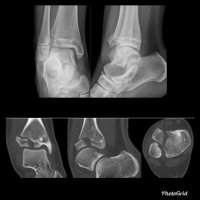

Avulsion fractures of the calcaneal tuberosity are uncommon, accounting for 1.3–2.7% of all calcaneal fractures.

The calcaneus is the primary weight bearing bone in the heel, and its many surface contours render it a relatively difficult bone to visualize in its entirety. The stabilizing ligaments that hold the calcaneus in place occupy very specific locations, and the Achilles tendon enthesis is in a relatively constant location; therefore, avulsion fractures occur in reproducible locations.

Fractures of the tuberosity are either from an avulsion or shear-compression mechanism of injury, with the latter constituting most fractures. Avulsion may occur from sudden tension on the Achilles tendon from falling on a plantarflexed foot when the calf muscles are actively contracted, hyperextension of the ankle, or while pushing off a dorsiflexed foot such as in a sprinter beginning a race.

There are four types of avulsion fractures: type 1, simple avulsion with a variable-sized bone fragment; type 2, beak fracture with a horizontal fracture extending into the posterior body; type 3, infrabursal avulsion by the superficial fibers of the middle third of the Achilles tendon; and type 4, small beak fracture avulsed from the deep fibers of the tendon.

An important pitfall is a neuropathic avulsion fracture of the tuberosity in a patient with long-term diabetes mellitus. In these patients, the fracture occurs without a history of significant trauma or overuse activity. The primary fracture line is parallel to the apophyseal scar, and the fracture affects the superior cortex but not always the inferior cortex.

The fracture also tends to extend posteriorly with a horizontal component immediately distal to the enthesis of the Achilles tendon. When the fracture is imaged sequentially, distraction and fragmentation are common later findings. Neuropathic fractures are important because they have a much higher incidence of infection, nonunion, malunion, and failure of fixation and require a much longer time to heal than nonneuropathic insufficiency fractures.

Another pitfall occurs in children. A Salter 3 fracture of the apophysis in a skeletally immature patient may mimic Sever disease when it is not significantly displaced. A systematic evaluation of the calcaneus with attention to areas of vulnerability will assist those who interpret ankle and foot radiographs in maintaining a high diagnostic accuracy for these fractures.

Typically, treatment is with open reduction-internal fixation (ORIF), although minimally displaced fractures may be treated with closed reduction.